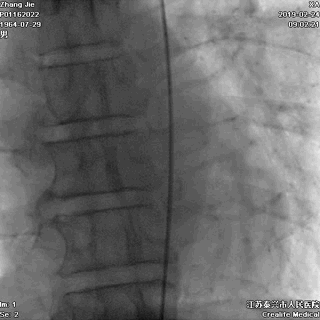

上)冠状动脉造影证实是左主干急性闭塞,术前心电图表现见上图。